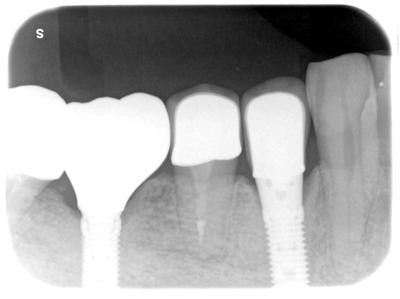

HOME > ブログ 一覧 > インプラント治療 2020.02.11インプラント治療 右下4部動揺激しく、本来の治療計画は抜歯、もしくは歯根のみ残して顎堤を温存、インプラントブリッジであったが、インプラントプロヴィジョナルを入れるとみるみる動揺が収束し、抜歯を回避した。 術後9年経過しているが、何の問題もなくメインテナンス中。 咬合力をインプラントがしっかり受け止め、力が分散しているケース。 使用インプラントは、Biomet 3i。 Recent Entries アライナー矯正(インビザライン、シュアスマイル)費用を2023年 1月から改訂させていただきます(01/09) 本年もよろしくお願いいたします(01/02) 年始の診療について(01/01) 新しいWEBへ移行、年末年始の診療のお知らせ(12/29) ダラダラ根管治療行っても治らないという事(12/21) Category その他の治療(126) インビザライン・矯正(52) インプラント治療(216) ホワイトニング(47) メインテナンス(21) 包括診療(95) 医院からのお知らせ(249) 審美治療(128) 日々雑感(283) 根管治療(100) 歯周病治療(90) 矯正(73) 補綴治療(45) 補綴治療カテゴリを追加(1) 診療全般(44) Archive 2023年1月(3) 2022年12月(6) 2022年11月(14) 2022年10月(6) 2022年9月(8) 2022年8月(7) 2022年7月(13) 2022年6月(8) 2022年5月(7) 2022年4月(7) 2022年3月(6) 2022年2月(7)